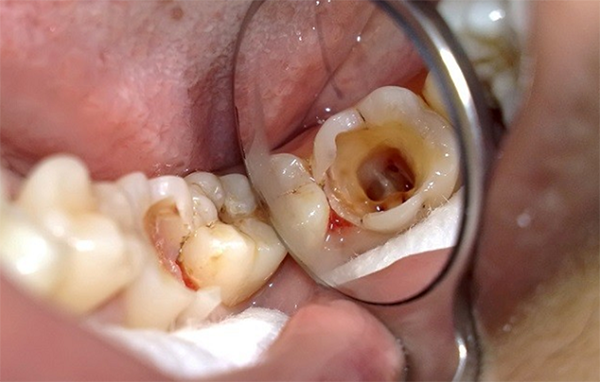

Đối với thể không đau của viêm tủy răng không hồi phục có thể phát hiện thông qua thăm khám lâm sàng khi thấy răng bị hở tủy có hiện tượng lốm đốm vàng, khối màu đỏ sẫm hoặc có lỗ sâu răng.

Khi khám lâm sàng, nếu là viêm tủy mạn tính thì bác sĩ sẽ phát hiện được nốt đỏ mọc giữa chân răng.